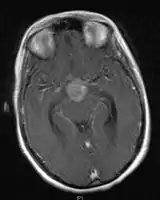

• Mainly located in midline structures, suprasellar region or pineal gland, also basal ganglia and hypothalamus

Location